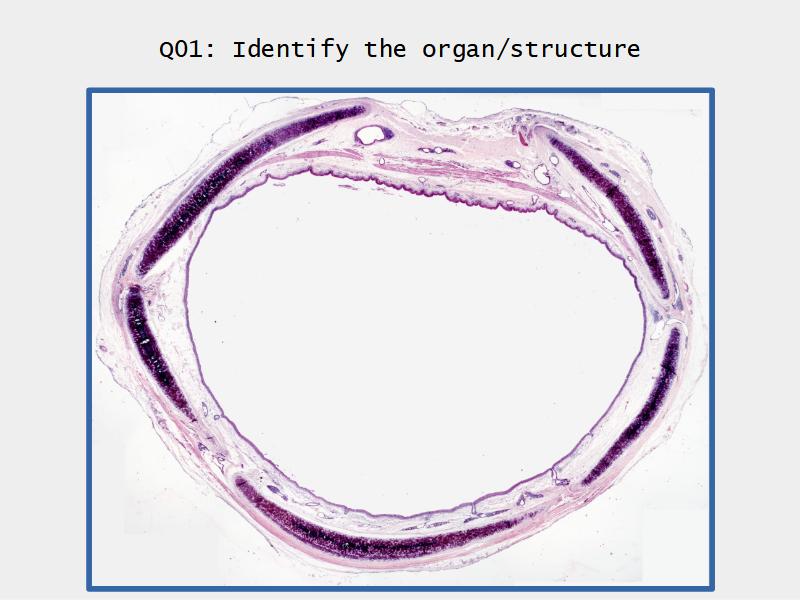

Slides: Respiratory System

- Slide 73: Trachea

Trachea